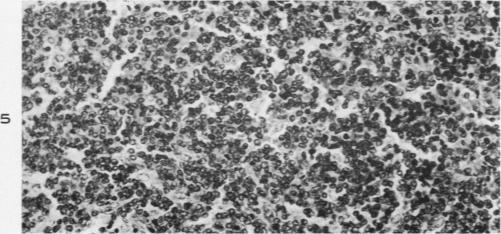

Leukemia in guinea-pigs.

Am J Pathol. 1954 Mar-Apr;30(2):337-59.